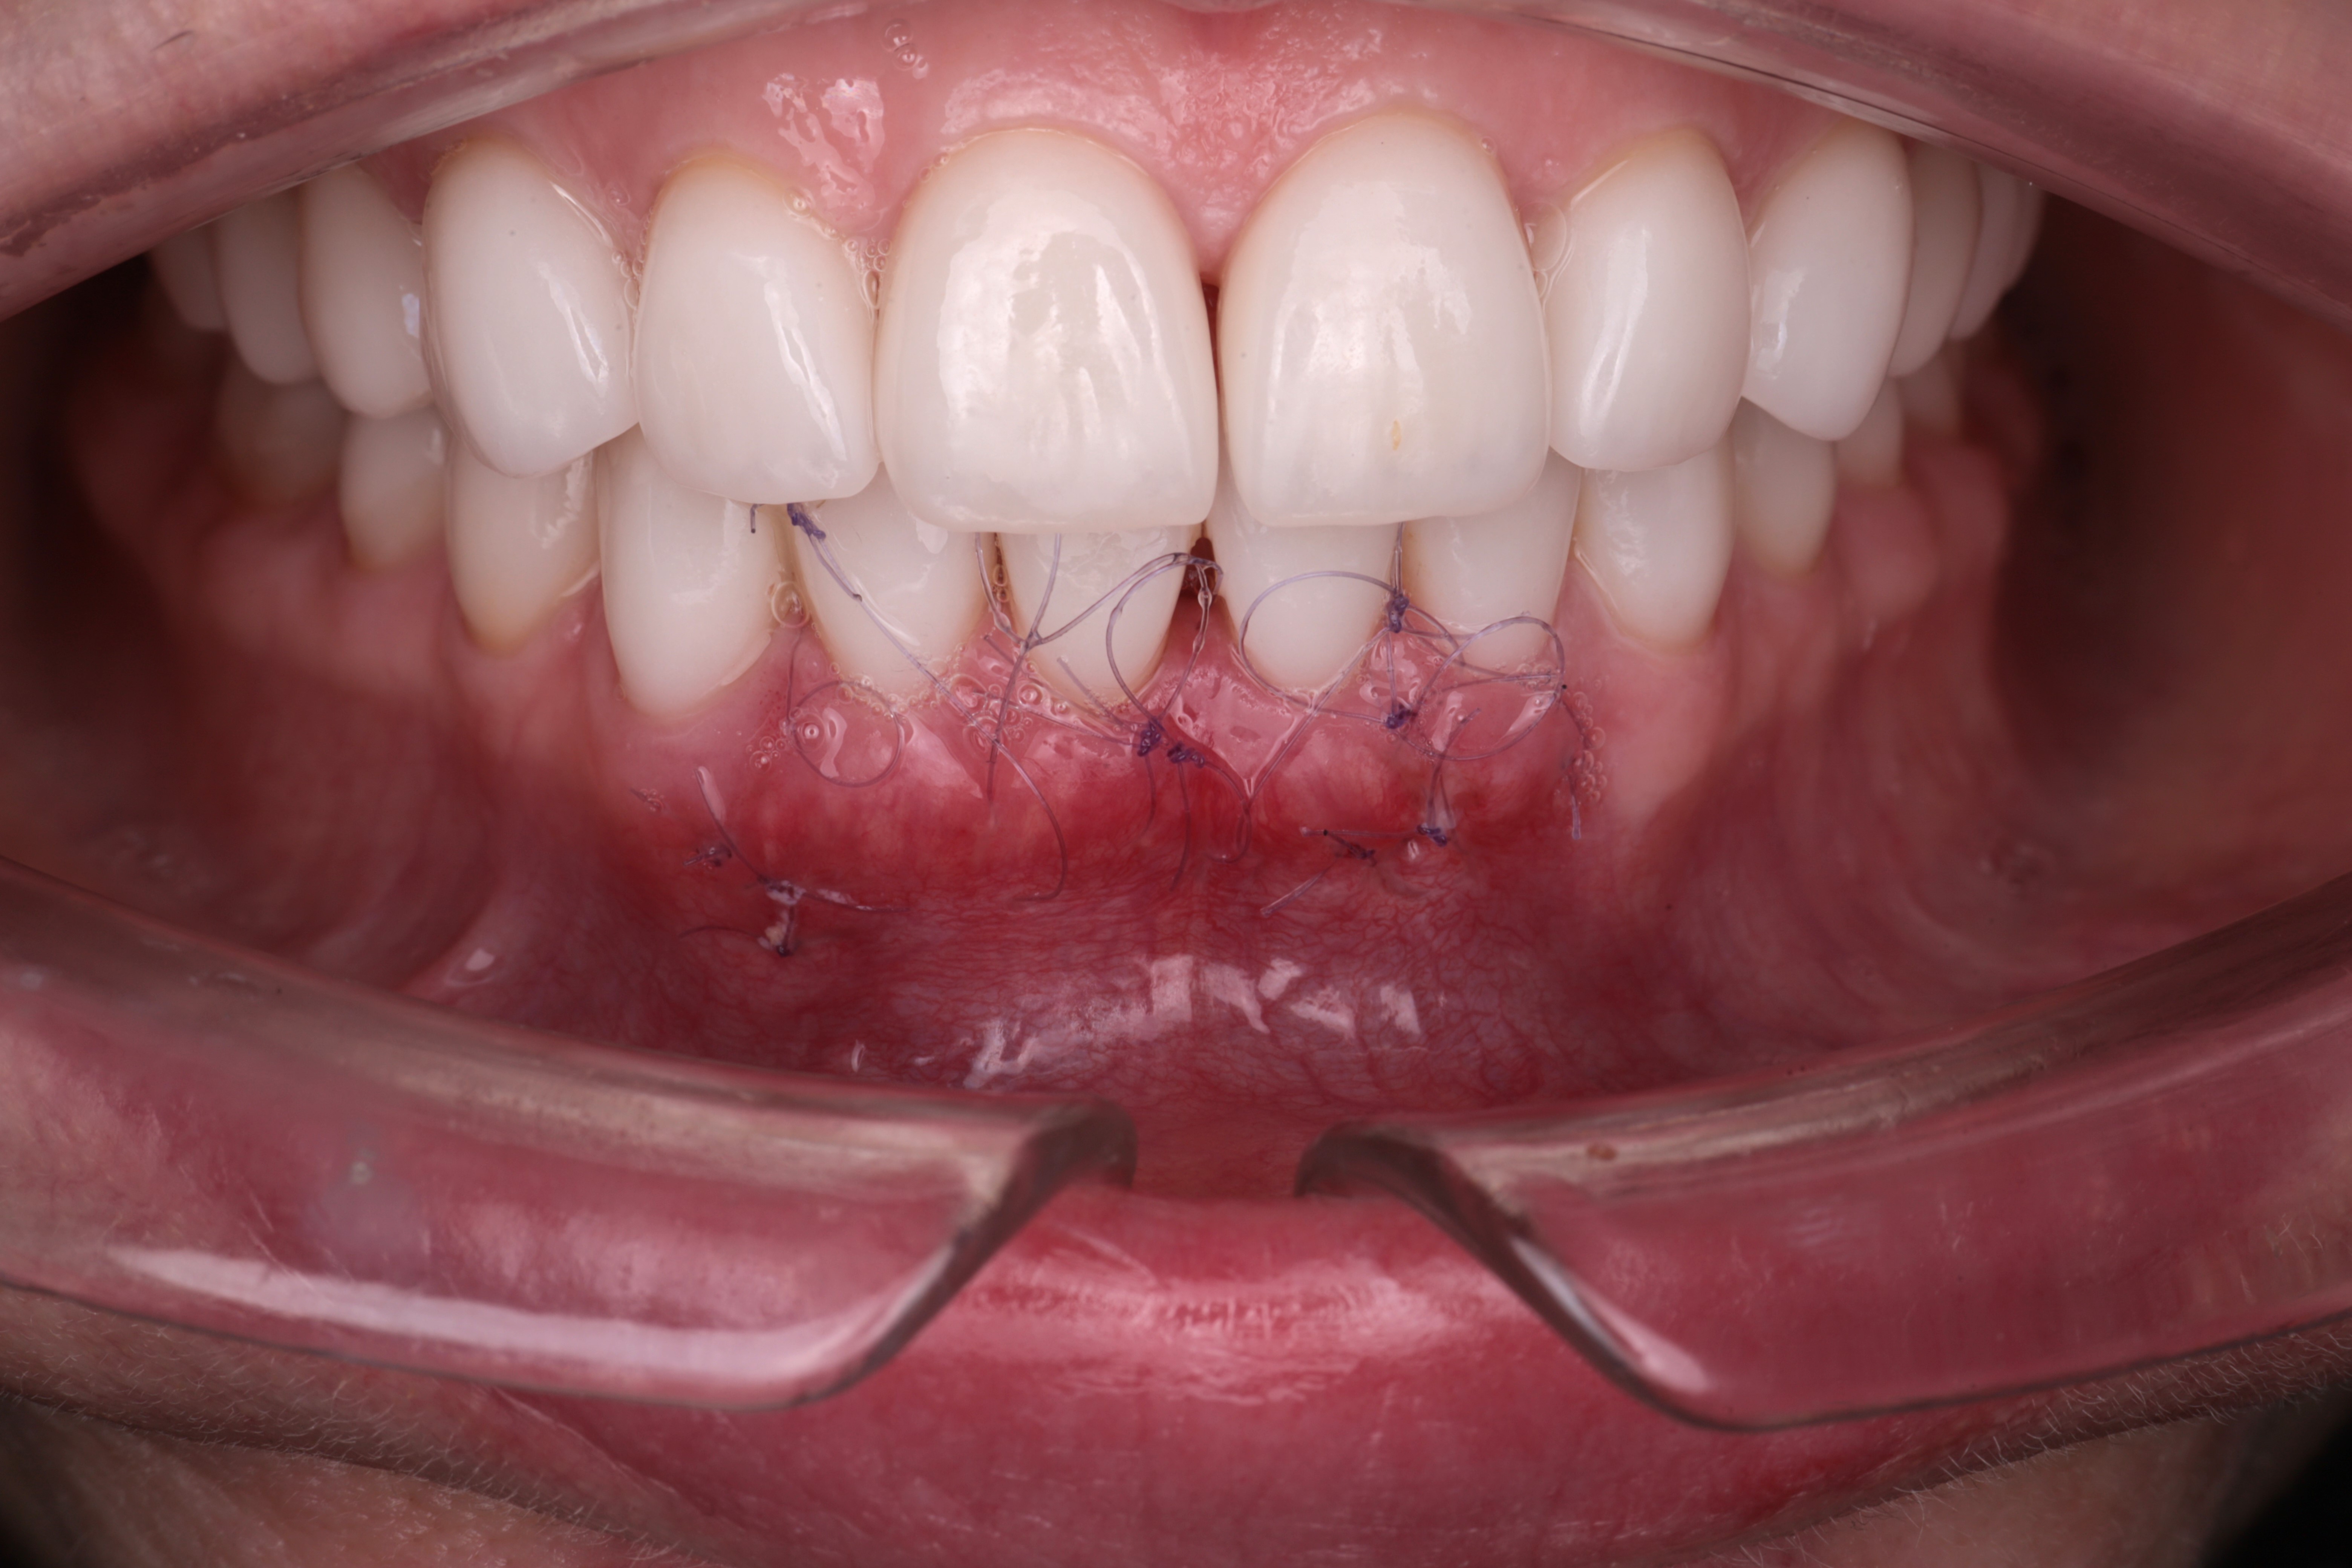

Ситуация через неделю после операции. Швы не состоятельны, рана выглядит удовлетворительно.